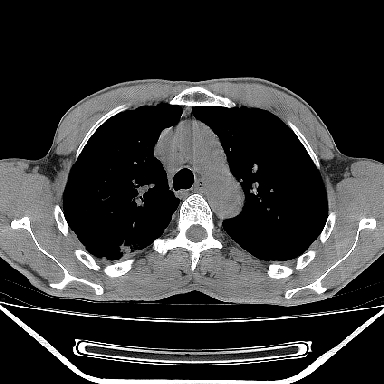

以下是引用lpc0ct在2006-11-28 16:12:00的发言:[br]大家图文并貌分析的太全面了,没有可说的,同意 [br] 右肺上叶中心型肺癌伴肺门、纵隔淋巴结转移.[br]

以下是引用dyqct在2006-11-28 16:00:00的发言:[br]右肺上叶中心型肺癌伴肺门、纵隔淋巴结转移。[br][br]